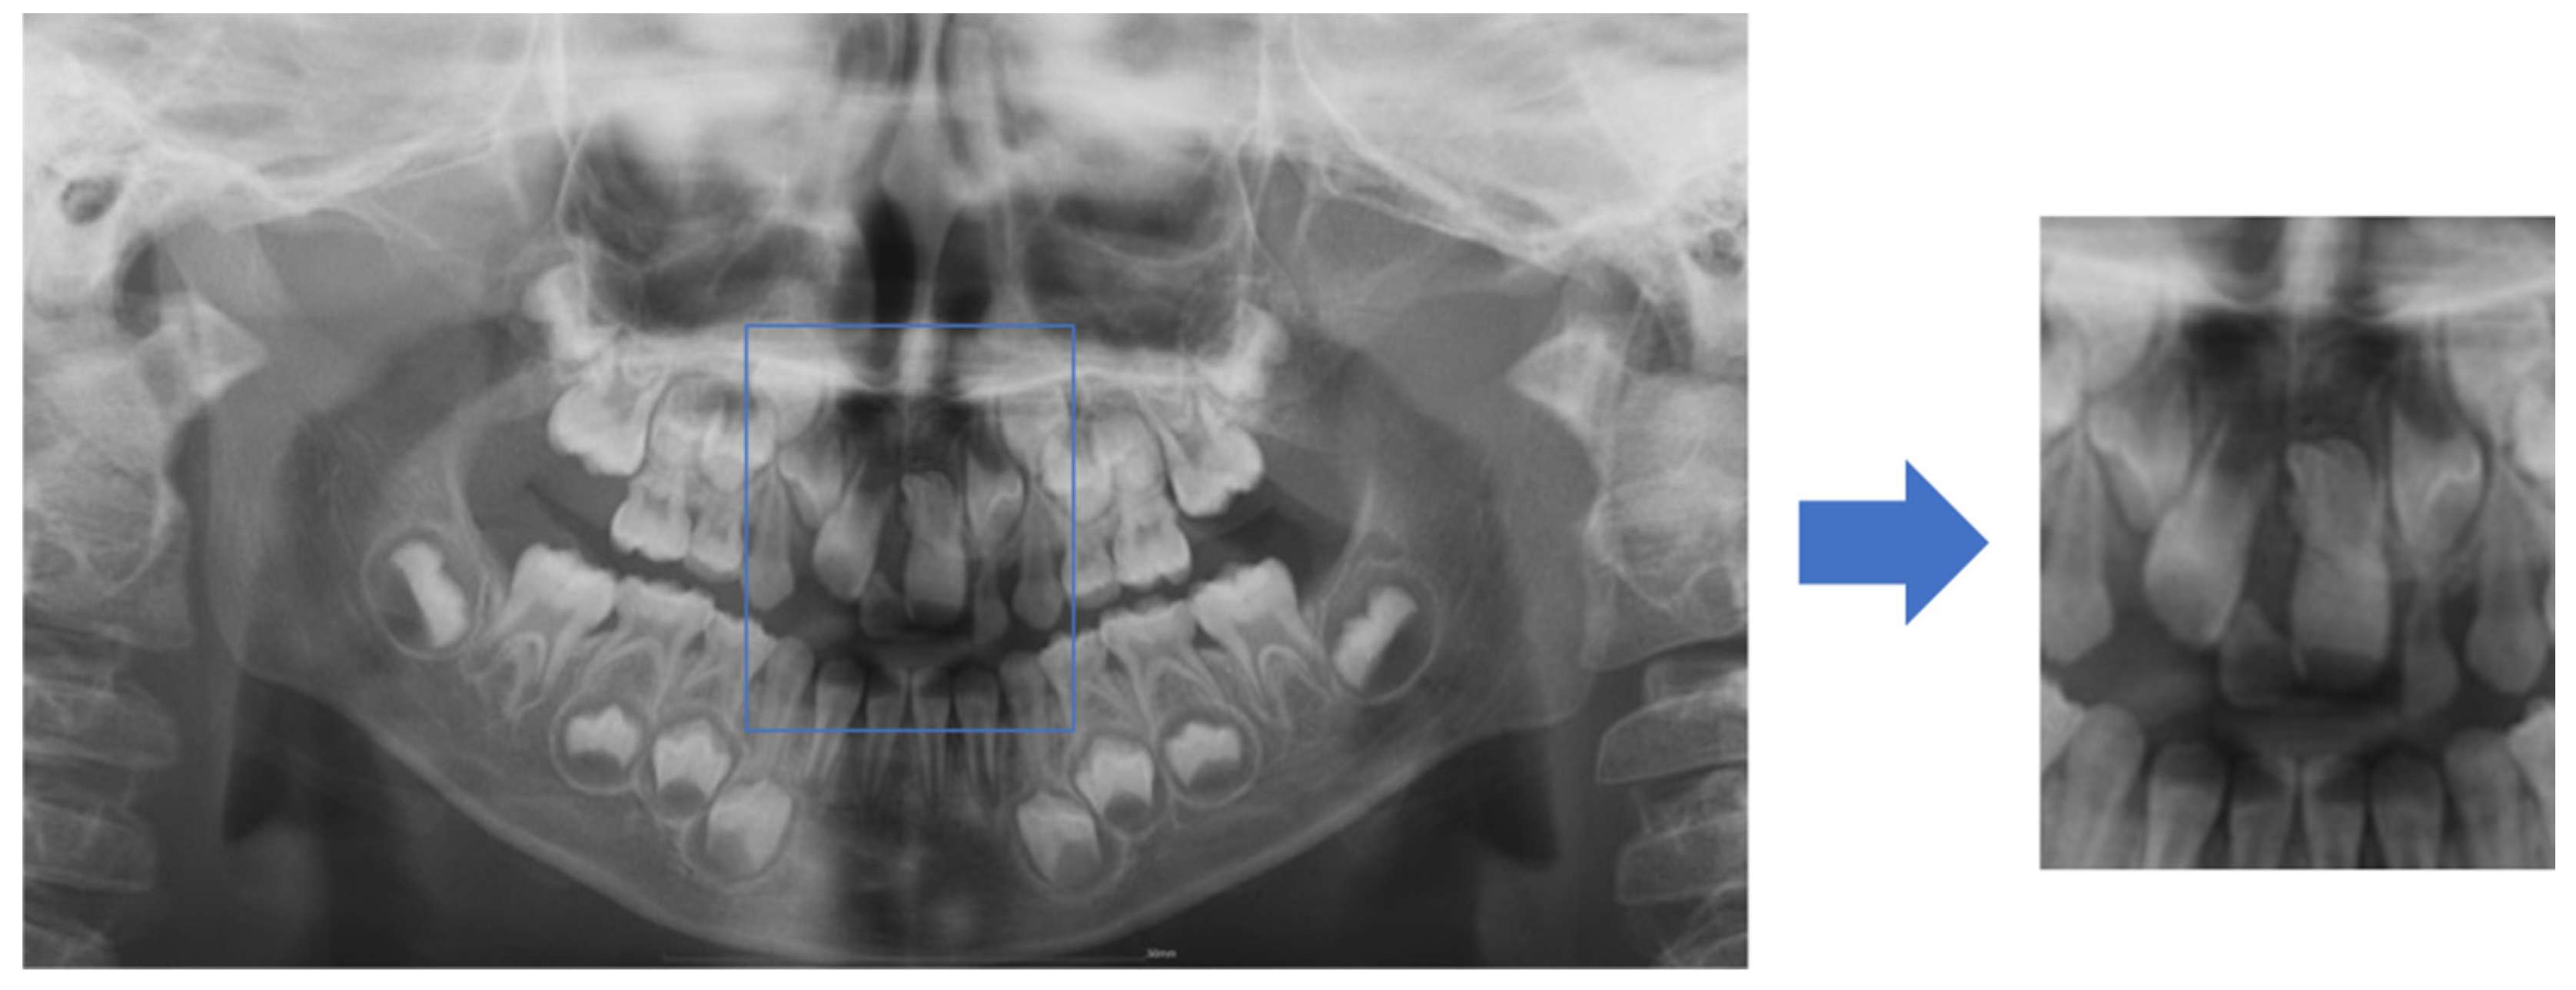

2.3.1. Data Preprocessing

2.3.2. Data Classification